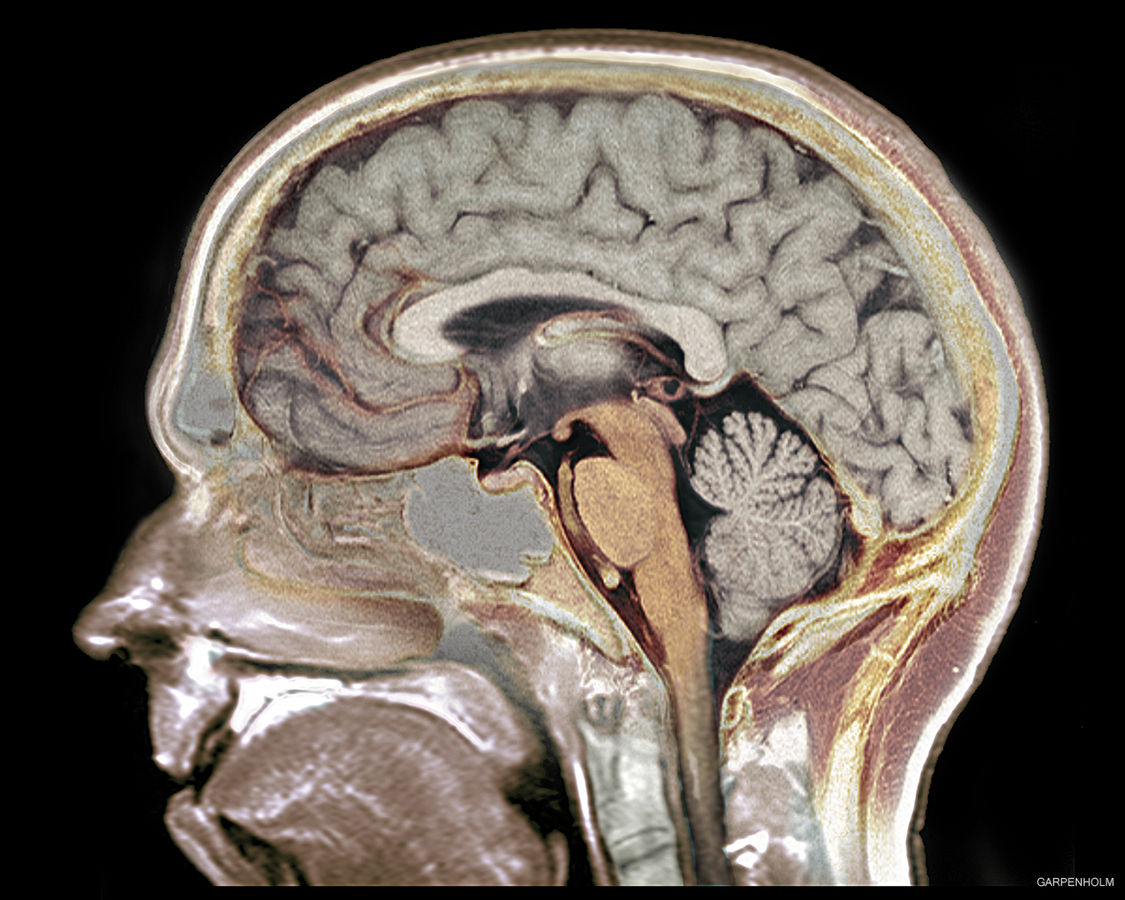

Brain scan.